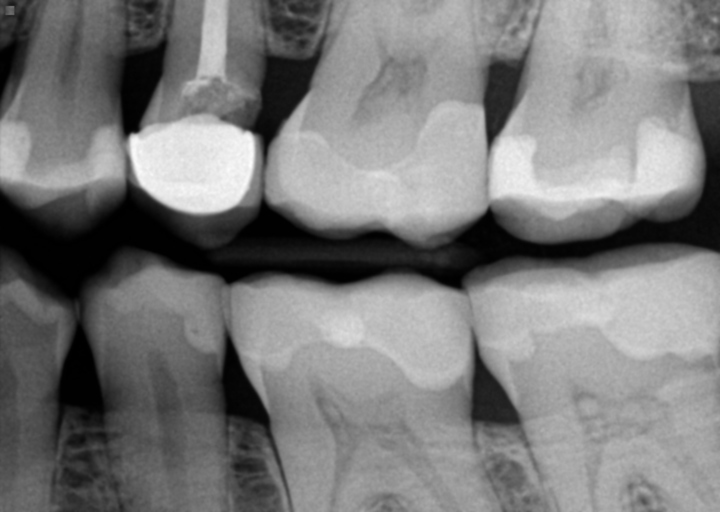

Had root canal done on top left molar 1 year ago and now it's throbbing and bleeding when I floss. Hurts when I bite down too...

After any tooth has a root canal, it is standard of care to place a full coverage restoration on the tooth, such as a crown. If you did not have a crown placed after the root canal, especially on a molar, there is a possibility that it is reinfected or fractured. If fractured, this could be the reason it is also bleeding, as the gum tissue around the tooth would get inflamed and result in bleeding as well as the pain when biting. If there is a full coverage crown on your tooth, it is also possible that the tooth can become infected if there was any contamination prior to placement or there is an accessory canal that may not have been treated. It is best to make an appointment with your dentist as soon as possible for a radiograph as well as other diagnostic testing to determine that cause and treatment. The tooth will only continue to worsen with time, so do not hesitate to make your appointment as soon as possible.